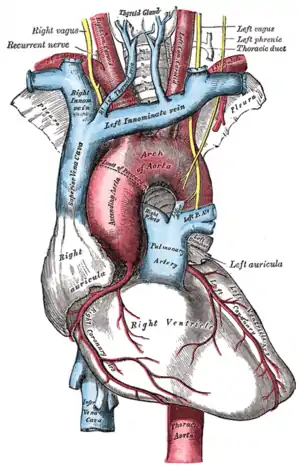

| The aorta, shown in red | |

Traumatic aortic rupture, also called traumatic aortic disruption or transection, is a condition in which the aorta, the largest artery in the body, is torn or ruptured as a result of trauma to the body. The condition is frequently fatal due to the profuse bleeding that results from the rupture. Since the aorta branches directly from the heart to supply blood to the rest of the body, the pressure within it is very great, and blood may be pumped out of a tear in the blood vessel very rapidly. This can quickly result in shock and death. Thus traumatic aortic rupture is a common killer in automotive accidents and other traumas,[1] with up to 18% of deaths that occur in automobile collisions being related to the injury.[2] In fact, aortic disruption due to blunt chest trauma is the second leading cause of injury death behind traumatic brain injury.[3][4]

By far the most common site for tearing in traumatic aortic rupture is the proximal descending aorta, near where the left subclavian artery branches off from the aorta.[7] The tethering of the aorta by the ligamentum arteriosum makes the site prone to shearing forces during sudden deceleration.[8]

A study of people who died after traumatic aortic rupture found that in 55–65% of cases the damage was at the aortic isthmus and in 10–14% it was in the ascending aorta or aortic arch.[4] An angiogram will often show an irregular outpouching beyond the takeoff of the left subclavian artery at the aortic isthmus, representing an aortic pseudoaneurysm caused by the trauma. Damage can also be in the lower thoracic or abdominal aorta.[4]